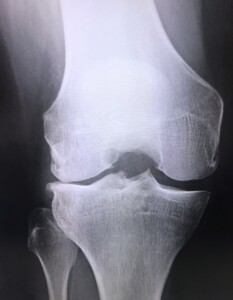

こうした悩みを抱えている方の中には、変形性膝関節症が進行しているケースが少なくありません。加齢や生活習慣の影響で膝関節の軟骨がすり減り、炎症や変形を起こす病気です。

1. 軟骨のすり減り

膝関節内のクッションである軟骨が加齢や負担の蓄積で摩耗し、痛みや炎症を生じます。

進行するとO脚が目立つ